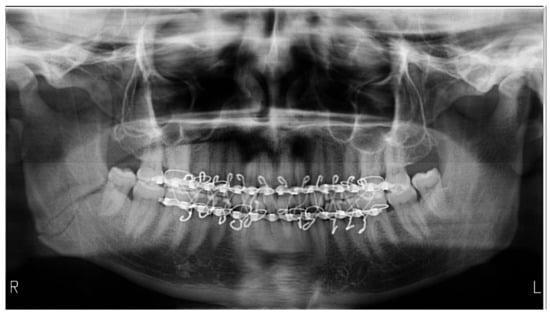

| Absence of bite-block | 28 | 93.33 | 51.85 | [78.68–98.15] |

| Positioning outside the focal plane | 21 | 70 | 46.66 | [52.12–83.34] |

| Radiographs with bimaxillary immobilization errors | 23 | 76.66 | 62.16 | [59.07–88.21] * |